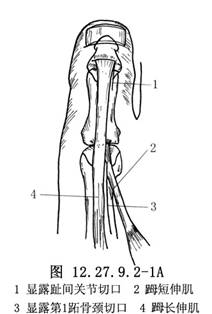

做“L”形切口显露𧿹趾趾间关节(图1a),将皮肤和皮下组织瓣向内、向近侧拉开,找到𧿹长伸肌腱。在趾间关节近侧1cm处横断肌腱,去除趾间关节面软骨,用一根直径为0.2cm的斯氏钉或两根直径为0.16cm的克氏针逆行固定,于皮下剪断内固定针。另做一个2.5cm长的足背内侧切口显露第1跖骨颈(图12.27.9.2-1A),注意保护𧿹短伸肌腱,并沿切口全长切开其腱鞘。在第1跖骨颈部位由跖内侧到外侧横向钻孔,将肌腱经孔穿过,调整合适张力后与自身做间断缝合(图12.27.9.2-1B)。